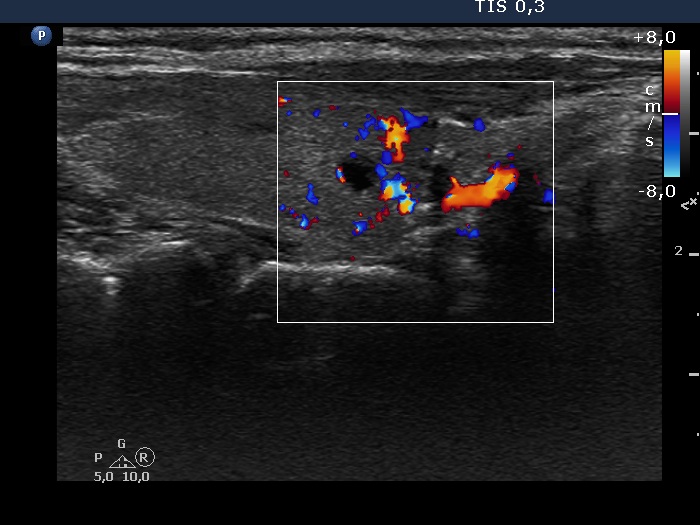

Intranodular hyperechogenic figures - case 1158

Nine months after the surgery (ultrasonographic picture 5)

Right lobe, longitudinal scan, color Doppler mode. There are large vessels around the moderately hypoechogenic lesion which has no vascularization.